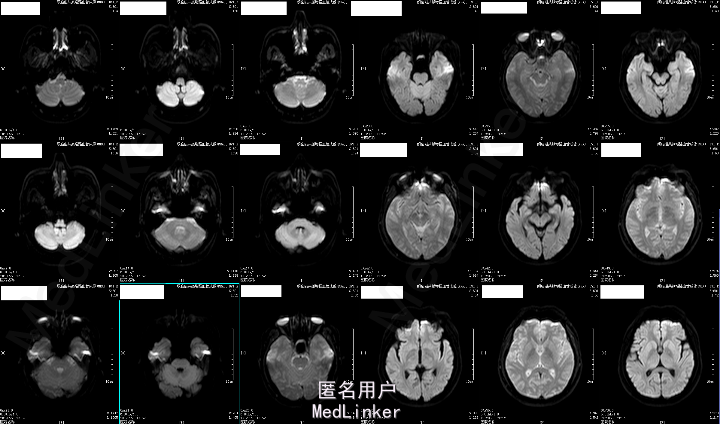

2015-05-26外院头颅MR:1.左额叶、枕叶病变考虑感染性病变可能性大(曼氏裂头蚴感染?)2.双侧上颌窦、筛窦慢性炎症。

2015-6-01我院头颅MRA:1.左侧额叶、枕叶及左侧基底节尾状核多发异常信号,考虑寄生虫感染(曼氏裂头蚴感染?)可能性大;2.左侧大脑前动脉A1段起始部稍狭窄;3.双侧筛窦炎症。

患者今年4月份时有吃“田螺、黄鳝”病史,既往有“高血压、糖尿病”,未规律治疗,结合其临床表现及头颅MRA“钻隧道”样改变,目前考虑“曼氏裂头蚴感染”可能性大。

成的中枢神经系统寄生虫病。I临床较为少见,易误诊。一般认为感染该病的途径有以下几种:食生或半生的蛙肉、蛇肉等(含裂头蚴);带有伤口的皮肤敷贴感染的生蛙皮、蛙肉等;饮用了含剑水蚤的生水。脑裂头蚴病的临床表现因感染部位的不同而各异。多以头痛、癫痫大发作及肢体活动障碍等为主,严重者可致颅内高压、视力损害、意识障碍甚至突然死亡。脑脊液检查可有蛋白及细胞数轻度升高。儿童脑裂头蚴病的病程一般不长,有些因虫体的迁延,其症状和体征也会发生改变。该病影像学表现多为单侧受累的单发病灶。病灶多位于皮质,也可侵犯脑室、脑干和小脑。活的虫体在脑内活动形成隧道、虫体分泌的产物及虫道周围的炎性反应使得该病影像学上具有一定特点:(1)主病灶一般较小,直径小于2 cm;(2)局部常伴发炎性反应,病灶周围脑实质可见不规则大片状水肿影;(3)MRI检查多表现为混杂长T1、长T2信号,临近侧脑室可变大,即所谓的“负效应”,增强扫描可见病灶呈匍行管状、串珠状、绳结状、扭曲条索状强化;(4)不同时期的影像学检查,病灶可在不同的部位;(5)CT检查可见点状钙化影,虽脑MRI对于钙化的显影不如CT,但也可表现出不均匀信号。脑裂头蚴病的病理学表现具有一定特点,裂头蚴幼虫在脑内迁徙游走形成坏死隧道,同时释放蛋白酶毒素溶解周围组织引起炎性反应,周围脑组织坏死后,局部炎性细胞浸润和纤维胶质细胞增生形成炎性肉芽肿。肉芽肿内可见有一条或数条虫体,虫体不分节,实体、无体腔,具有特征性的体壁结构是散在分布的椭圆形石灰小体及束状纵行肌纤维,前者可能为虫体的残骸。裂头蚴抗体血清免疫学检查(ELISA法)具有高度的特异性和敏感性。手术摘除裂头蚴为该病最有效的治疗手段,可